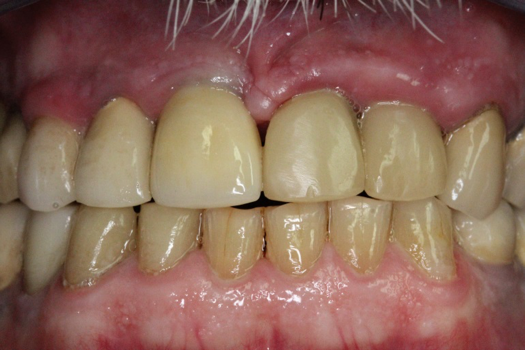

Fig 6. Image of the patient’s mature smile.

Figure 6

Figure 6 and Figure 7 depict a mature smile with many implant restorations. An analog impression was sent to the laboratory. The impression was scanned by the laboratory, a model was created virtually, and the implant dimensions and position were defined. The 3D surgical guide was fabricated (Figure 8), allowing the patient to receive his therapy swiftly and predictably. Tooth No. 8 was extracted, and the implant was placed and immediately loaded with an acrylic provisional treatment crown (Figure 9). The screw-retained treatment crown was fabricated in-office from a previously completed diagnostic wax-up.